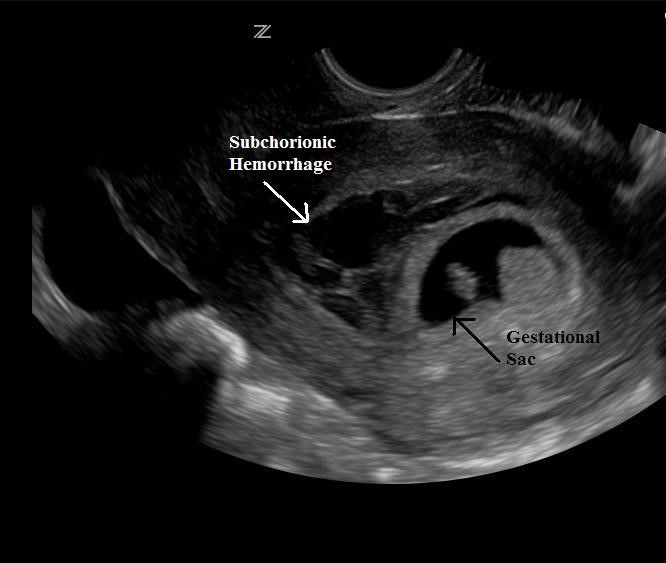

- Subchorionic Hemorrhage

- Frequent cause of first and second trimester bleeding19

- Anechoic/Hypoechoic crescent around gestational sac (Illustration 18)

- Illustration 18. Subchorionic hemorrhage

Increased risk of miscarriage20,21